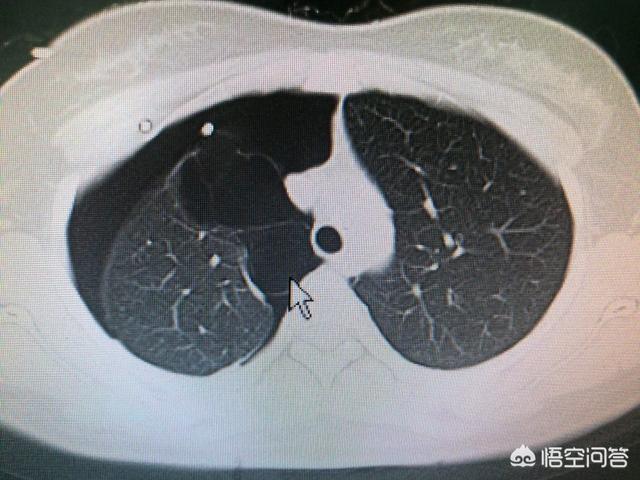

支气管哮喘的个体差异比较大,有相当大一部分可以突然发作以及自然缓解,所以往往容易被忽视。 而自发性气胸也是年轻人最常见的一种疾病,一般指的是胸膜腔呈积气的状态,也就是说胸膜腔密闭腔体被破坏进入了气体,从而会引起胸闷气促,呼吸不畅等症状。

自发性气胸产生的最常见诱因有:剧烈咳嗽、用力、剧烈运动等等,一般可伴有胸痛症状,根据气体的多少,症状轻重有所不同,大量的气胸,可引起明显的呼吸困难,甚至呼吸衰竭,一般行胸片可以看到胸膜腔气体,可以确诊。